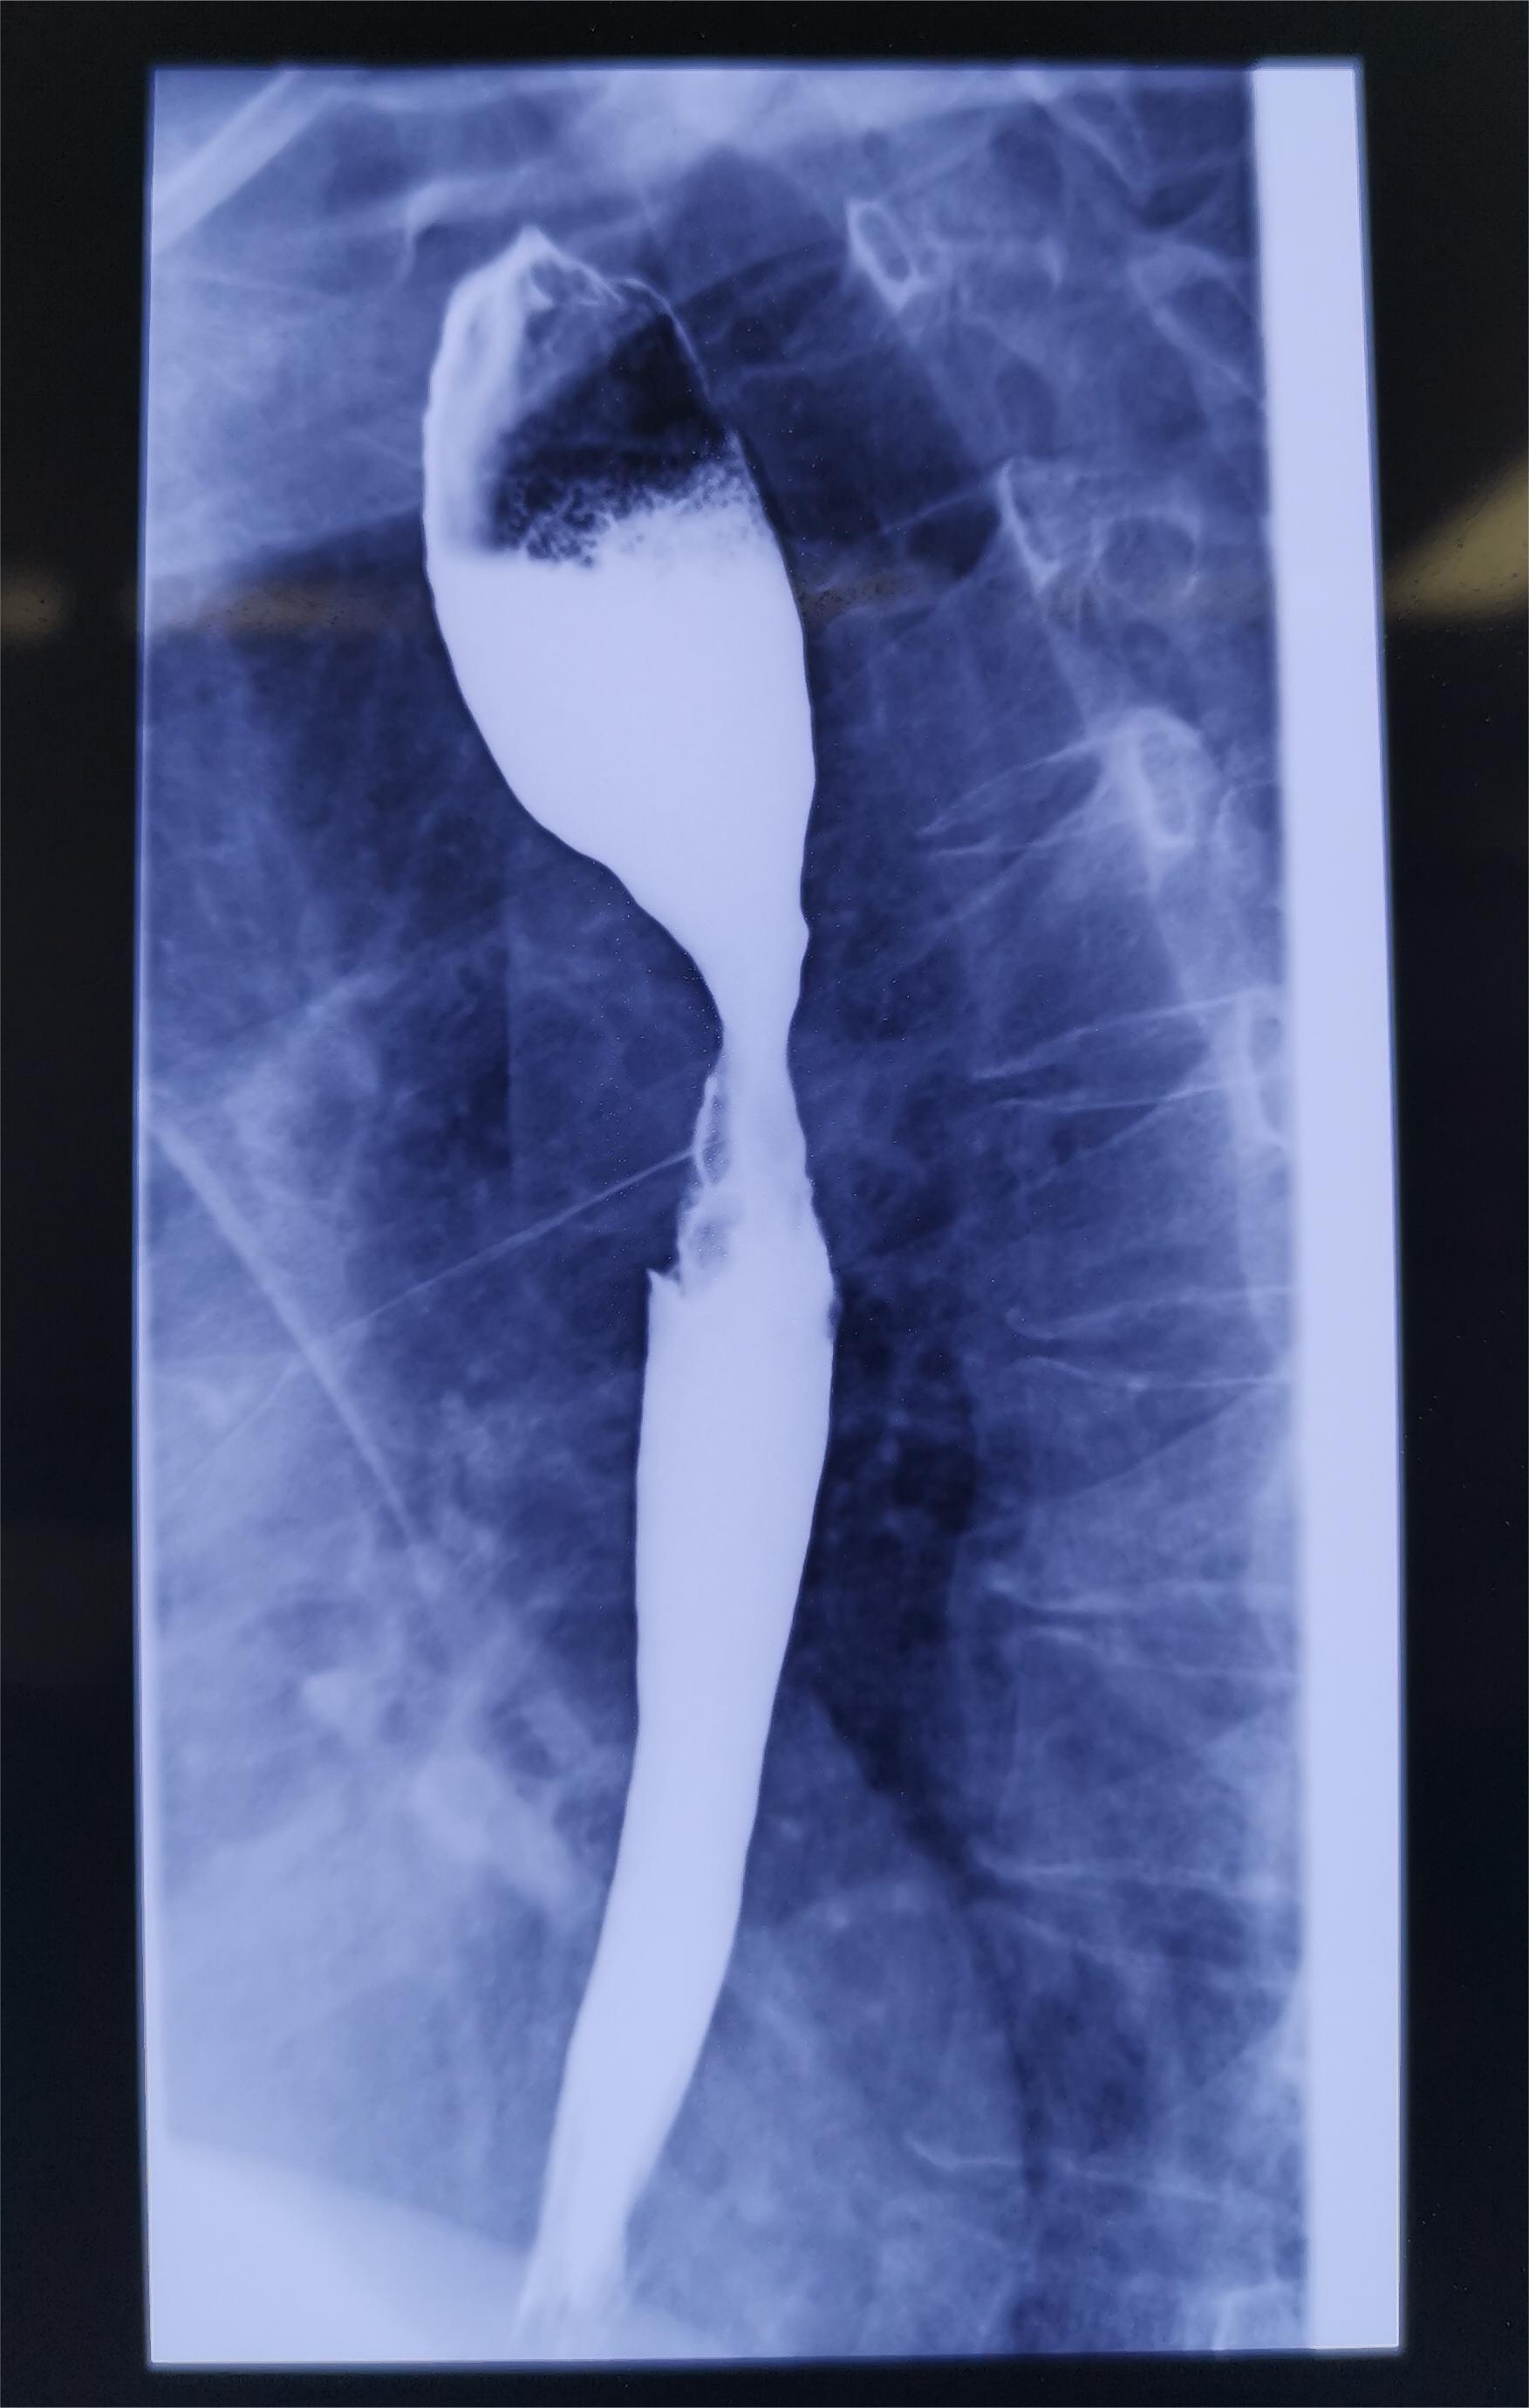

食管癌是人類常見的惡性腫瘤之一,多見于六七十歲的老年人,5年生存率小于10%。我國食管癌的發(fā)病率目前居世界第一位,發(fā)病人數(shù)占發(fā)病總數(shù)的60%,且男性的發(fā)病率是女性的兩倍。我省食道癌發(fā)病率居高不下,尤以桐城、廬江等地為高發(fā)地區(qū)。誘發(fā)食管癌的危險(xiǎn)因素包括飲食習(xí)慣、環(huán)境因素、家族史等多方面作用。長期嗜食過于辛辣、偏硬、過熱和制作粗糙的食物、進(jìn)食過快、飲烈酒、吃大量胡椒,這些對食管黏膜的慢性刺激,在不斷的損傷、修復(fù)過程中,容易引起癌變。 傳統(tǒng)常用的食管癌根治術(shù)有左經(jīng)胸一切口,右經(jīng)胸、經(jīng)腹二切口,右經(jīng)胸、經(jīng)腹、經(jīng)頸三切口等術(shù)式,胸腹部手術(shù)的切口長,創(chuàng)傷大,術(shù)后并發(fā)癥多。而在臨床上,對于腫瘤小于5厘米,無明顯外侵的早期和中期食管癌,可以通過胸腔鏡和腹腔鏡可以順利完成食管切除和縱隔淋巴結(jié)清掃術(shù)。胸腹部無長切口,術(shù)后病人出血少,疼痛輕,心肺并發(fā)癥減少,恢復(fù)快,手術(shù)符合美學(xué)要求。 胸腔鏡手術(shù)不僅局限于早期食管癌的治療,還廣泛應(yīng)用于早期肺癌、肺孤立性小結(jié)節(jié)、氣胸、肺大泡、縱膈腫瘤、手汗癥等疾病的診治。

食管癌(又稱食道癌)離我們每個人都很遠(yuǎn),但似乎又很近。遠(yuǎn)的是從全世界疾病譜來看與肺癌、乳腺癌等相比發(fā)病率并不高。近的是食管癌是有明顯地域分布性的。拋開其他國家不說,國內(nèi)河南省食管癌發(fā)病率及死亡率最高,云南省的卻最低。而安徽、四川、廣州、河北等都是食管癌高發(fā)區(qū)域。醫(yī)學(xué)發(fā)展很慢,慢到很多疾病都找不到明確的原因,食管癌目前公認(rèn)的致病因素大致上是:1、吸煙、飲酒。這與我國最常見的食管鱗狀細(xì)胞癌密切相關(guān)。2、食物中的致癌物質(zhì)。硝酸鹽類物質(zhì)(如腌制肉制品、泡菜及變質(zhì)蔬菜等)的攝入過多會誘發(fā)食管癌。別的省份不說,就安徽而言,咸肉、香腸、雪里紅哪個不是徽菜的重要元素之一?3、遺傳因素。研究發(fā)現(xiàn)食管癌是有遺傳性的,也就是哪怕咱們這輩人已經(jīng)預(yù)防性的不再去接觸前兩條里的致病因素,仍然不能完全逃過食管癌的魔掌。4、其他:感染因素、微量元素和礦物質(zhì)缺乏。進(jìn)食刺激性食物較多或燙食過快過多。食管癌也同其他腫瘤一樣,有一個發(fā)展的過程。很可惜早期大部分人沒有任何癥狀,或者癥狀非常不典型,很難讓人聯(lián)想到這種疾病。而到有了典型癥狀的時候大部分患者已經(jīng)進(jìn)入了中晚期。食管癌的經(jīng)典癥狀是進(jìn)行性加重的進(jìn)食哽咽感。而早期可能僅僅是進(jìn)食有異物感、噯氣、反酸和輕微胸痛。常飲酒的人常出現(xiàn)此類癥狀,所以并不能代表什么,但是卻足以引起重視。確診食管癌的最好的檢查是胃鏡。個人建議有家族史的人到了40歲以上的每年最好能做一次作為常規(guī)體檢。早發(fā)現(xiàn)早治療,甚至可以在消化內(nèi)科進(jìn)行內(nèi)鏡下治療食管癌內(nèi)鏡下粘膜剝離術(shù)/粘膜切除術(shù)(ESD/EMR)就可治愈。但是一旦內(nèi)鏡下無法切除,我們胸外科食管癌根治術(shù)便是唯一能達(dá)到治愈效果的治療途徑。如果發(fā)現(xiàn)的時候已經(jīng)錯過了最佳手術(shù)時機(jī),只有求助放療、化療、免疫治療等治療方案來試圖降期治療,治療過程中再尋求根治的機(jī)會。食管癌根治的手術(shù)已經(jīng)進(jìn)入了微創(chuàng)時代,開放手術(shù)未被淘汰但已經(jīng)不作為首選方案了。具體手術(shù)方案和過程不是本次宣教的主要內(nèi)容。食管癌經(jīng)過有效治療后,總體5年生存率為20%左右。目前食管癌的切除率為58%~92%,手術(shù)并發(fā)癥發(fā)生率為6.3%~20.5%;切除術(shù)后5年和10年生存率分別為8%~30%和5.2%~24%。臨床分期將食管癌分為IV期,我們說的早期一般指I期到IIa期,手術(shù)后5年生存率能達(dá)到90%以上。如果是IIb期到IIIa期,雖然也可以手術(shù),但5年生存率不到30%。如果到了IV期,則生存率很低,手術(shù)方案遠(yuǎn)不及放療、化療、免疫等保守治療。在我國,50%的患者在診斷時已為晚期,此時預(yù)后很差,自然病程僅有6~8個月,5年生存率為5%~7%。即使接受了手術(shù)治療,仍有近90%的患者術(shù)后存在復(fù)發(fā)轉(zhuǎn)移的現(xiàn)象。因此,早期診斷治療非常重要。安徽醫(yī)科大學(xué)第一附屬醫(yī)院(高新院區(qū)和績溪路院區(qū))普胸外科作為安徽唯一首批上榜“中國食管癌外科高質(zhì)量臨床研究協(xié)作組”和“國家癌癥中心食管癌診療質(zhì)控示范單位”,在食管癌手術(shù)治療技術(shù)上全國領(lǐng)先,每年食管癌手術(shù)量超過1200臺,作為高質(zhì)量診療單位也隨時歡迎您的咨詢。本文作者門診時間:周日上午安醫(yī)大一附院高新區(qū)門診。